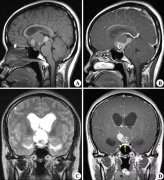

颅咽管瘤占儿童脑肿瘤的 5% 到 15%,成人占 1%。脑垂体区域容易发生颅咽管瘤,可能影响内分泌功能。此外,它们靠近视神经和视交叉可能会导致视力问题。一些患者出现由三脑室...

颅咽管瘤是一种少见的脑肿瘤,通常发生在垂体附近和下丘脑,他们是良性的、缓慢生长的肿瘤,很少扩散到大脑的其他部位。然而,由于对附近大脑结构的影响,肿瘤可能有害。...